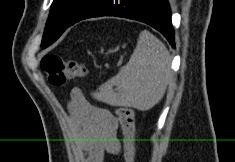

Нативная КТ (бесконтрастное исследование селезенки) показывает структуру органа достаточно однородно, без выявления незначительных изменений. Для большей информативности делают КТ селезенки с применением контрастных веществ.

На томограмме можно увидеть:

- нарушение целостности селезенки;

- кисты и крупные опухоли;

- кальцинаты;

- травматические и посттравматические изменения селезенки

- кровоизлияния внутрь брюшной полости

- отклонения от нормальных размеров.

- дополнительные дольки селезенки.